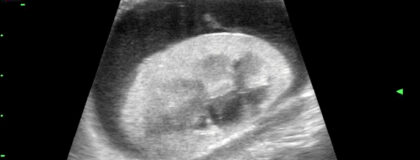

In diesem vetinar wird die Sonographie der Nieren bei Hund und Katze praxisnah vermittelt. Die Teilnehmer:innen lernen, wie normale Nierenstrukturen im Ultraschallbild aussehen und welche typischen Merkmale auf pathologische Veränderungen hinweisen. Schwerpunkte sind unter anderem die Diagnostik von Nierensteinen, Zysten, Tumoren sowie Anzeichen für chronische Nierenerkrankungen. Es werden sowohl gesunde Nierenbilder als auch häufige pathologische Befunde detailliert besprochen, um eine sichere Differenzierung und Diagnose zu ermöglichen. Ziel ist es, die Teilnehmer:innen in der Durchführung und Interpretation der Nierensonographie zu schulen, um eine schnelle und präzise Diagnosestellung zu fördern.